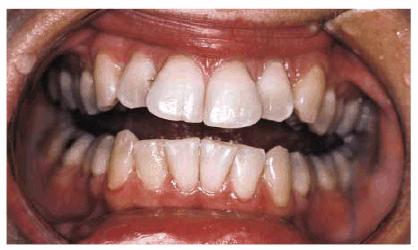

PROBLEM: This 30-year-old horse trainer had extremely large central

incisors (Figure 24-3A). In addition, the mandibular

centrals were crowded and rotated lingually (see Figures 24-3A, and 24-3B

Figure 24-3A: This 30-year-old woman had extremely large central incisors with overlapping maxillary and mandibular teeth.

Figure 24-3B: An occlusal view showing the overlapping central incisors.